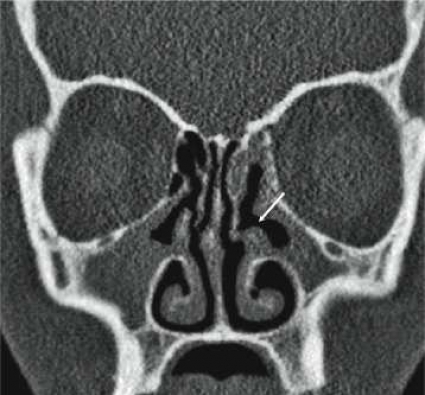

Initiala fantomstudier och pilotundersökningar visade, som förväntat, att bildkvaliteten med lågdosprotokollet blev sämre än med standardprotokollet, men den bedömdes ändå som fullt tillräcklig för den diagnostiska uppgift som avses med en konventionell röntgenundersökning av bihålorna (Figur1). Det diagnostiska värdet av lågdos-DT bedömdes av både radiologer och örondoktorer som klart överlägset värdet av en vanlig röntgenundersökning, och dosberäkningar visade också att stråldosen var lägre för lågdos-DT än för konventionell röntgenundersökning.

Användandet av lågdos-DT innebär sålunda inte bara en säkrare diagnostik av bihåleförändringar än med vanlig röntgenundersökning, utan man får också viktig tilläggsinformation, som inte kan erhållas med vanlig röntgenundersökning. Även möjligheten att visualisera små, men kliniskt relevanta anatomiska avvikelser (tex concha bullosa, Haller-celler och dysplasier), postoperativa förändringar, benförändringar vid kronisk sinuit och odontogena orsaker till sinuit, gör lågdos-DT klart överlägsen konventionell röntgenundersökning vid sinuit (Figur2).